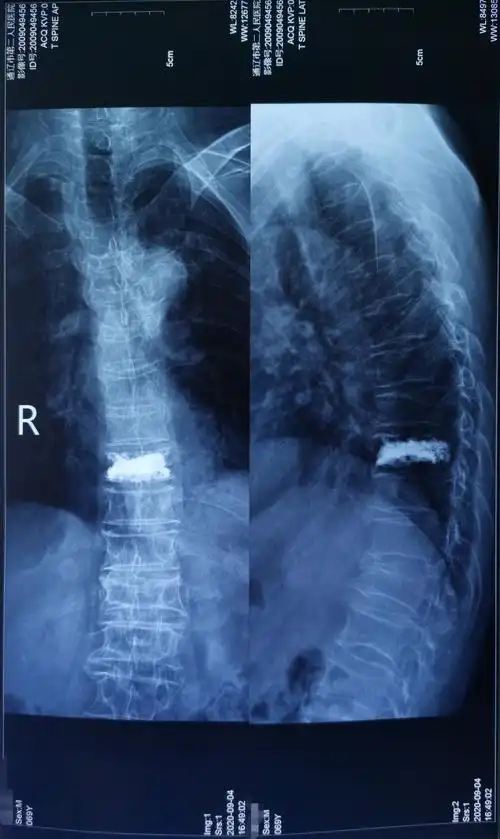

市第二人民医院骨外科为71岁胸9椎体压缩性骨折患者行椎体成型手术,术